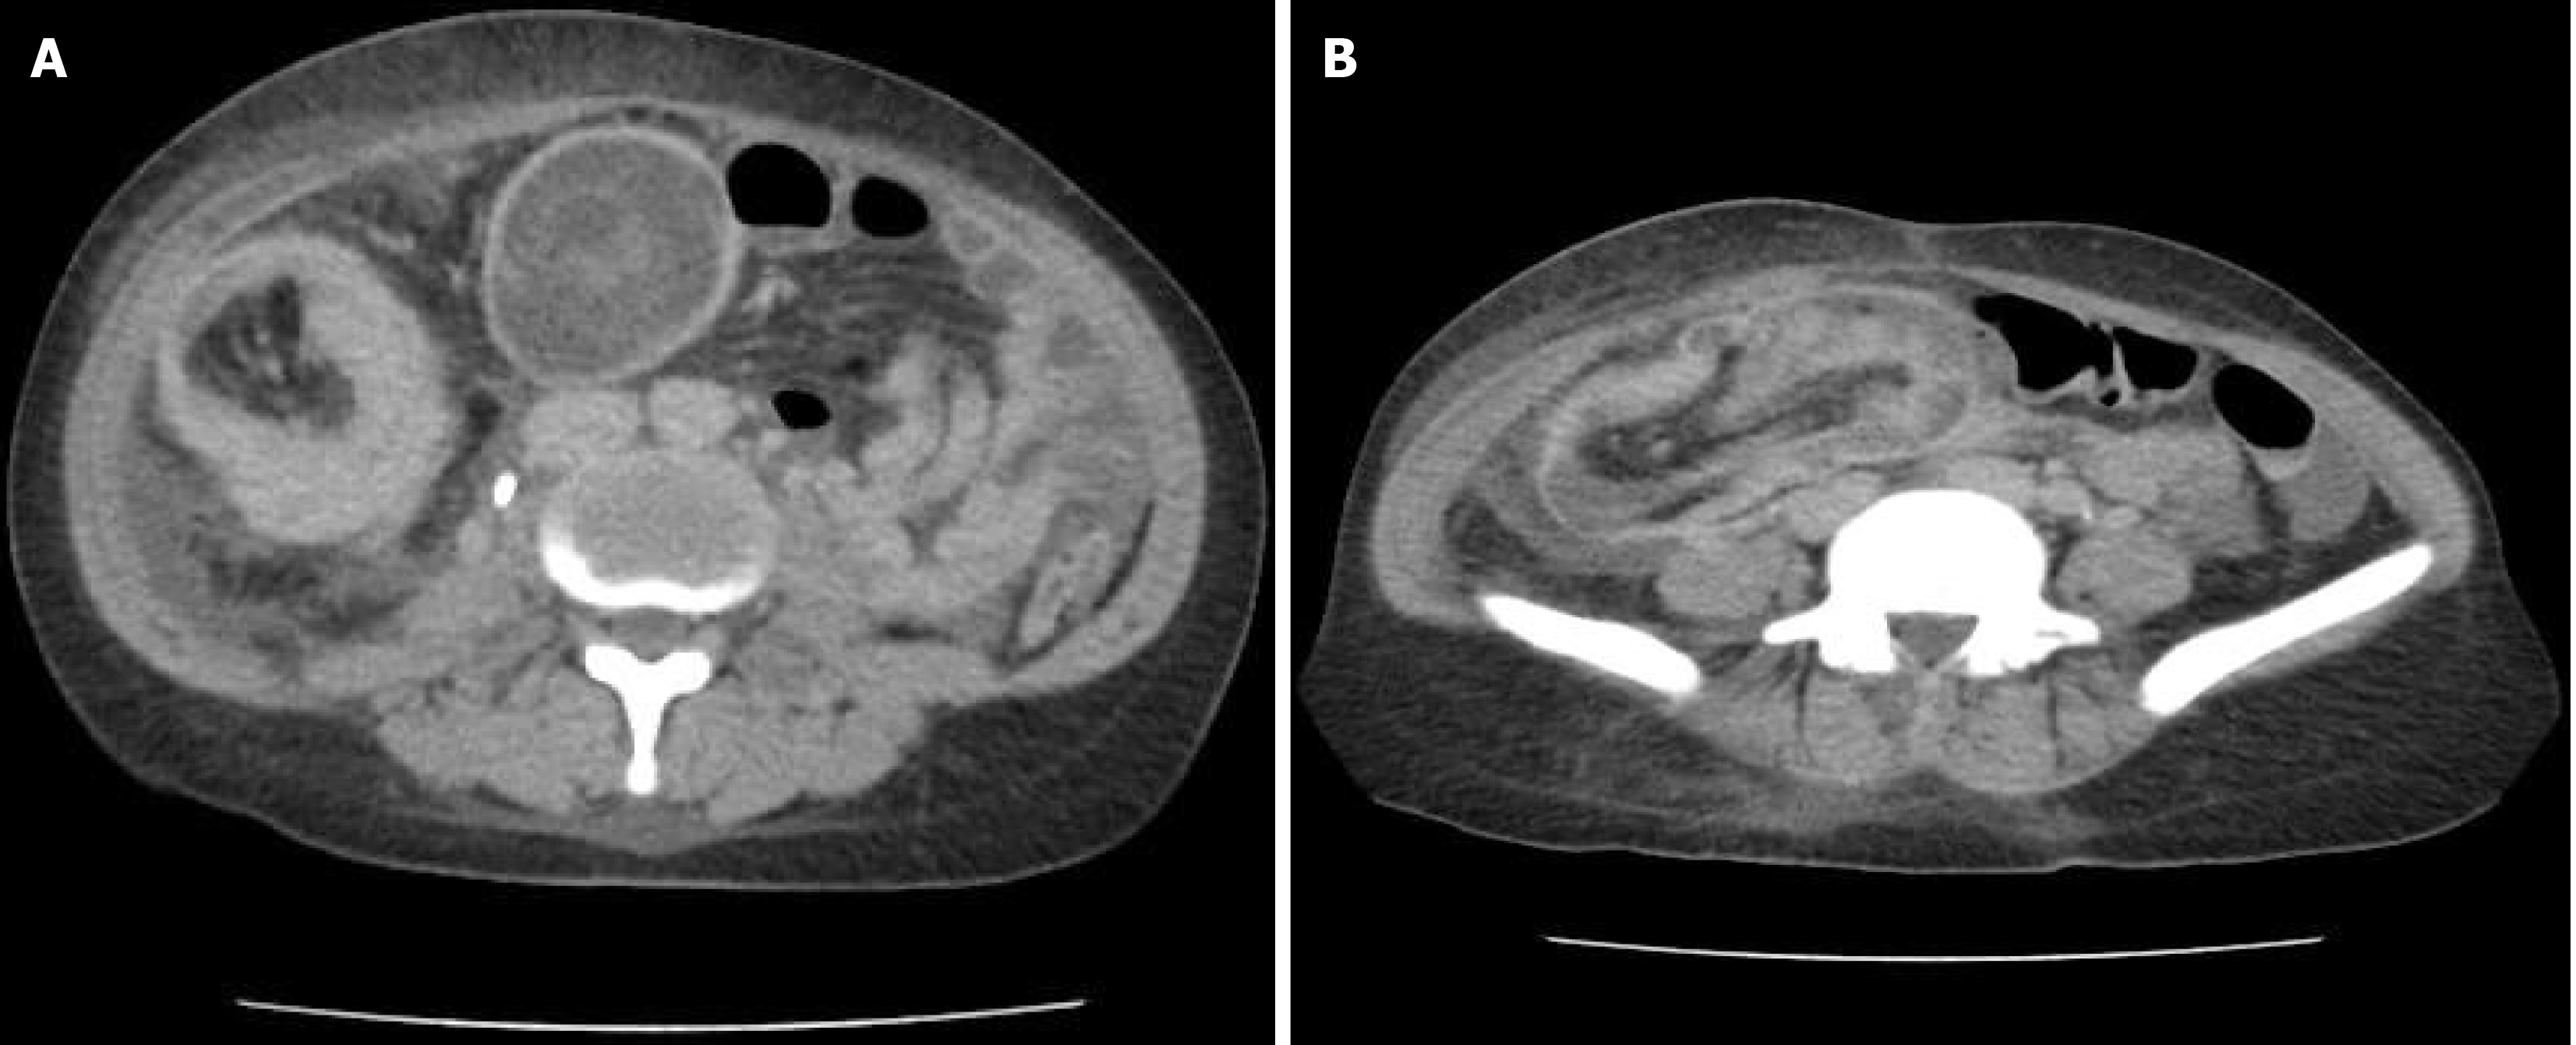

Figure 1 Computed tomography abdominal scan.

A: A mass in the cecum and ascending colon; B: Ileal invagination into the cecum.